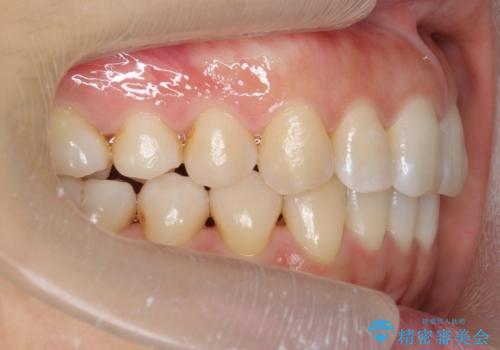

下の前歯のがたつき インビザラインで

- 前歯のがたつきを主訴に来院。

インビザラインで上下の前歯をわずかに削って並べました。

下の歯の叢生を並べると多少ブラックトライアングルがでることがあります。